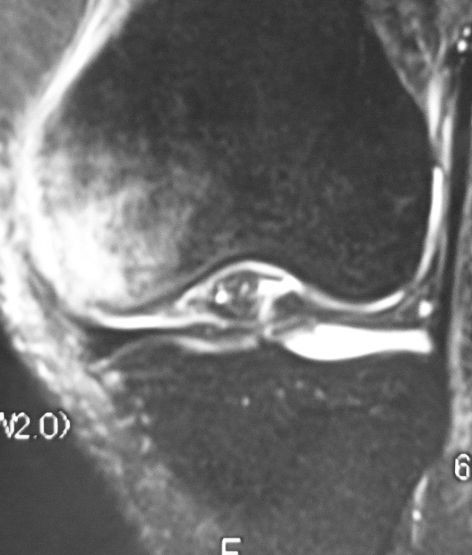

Mriによる膝関節部骨壊死症の検討 臨床整形外科 25巻10号 医書 Jp

だいたい、変形性膝関節症なんですけど 今回は 、その中で "膝関節特発性骨壊死" をみかけました。 これはどういったものなのか、まとめていきます。 どんな病気? 膝関節に激痛・水症・可動域制限をきたす高齢者の退行性膝関節疾患である。だいたい、変形性膝関節症なんですけど 今回は 、その中で "膝関節特発性骨壊死" をみかけました。 これはどういったものなのか、まとめていきます。 どんな病気? 膝関節に激痛・水症・可動域制限をきたす高齢者の退行性膝関節疾患である。Vol3 特発性膝関節骨壊死症 膝関節に発生する局所的な軟骨下骨の骨壊死です。原因が特定できない特発性とステロイド性による二次性に分けられます。 病態・症状 中年から高年の女性で大腿骨内側顆部の荷重部に発生することが多いです。 突然の膝関節痛

脛骨顆部骨壊死様病変は大腿骨顆部骨壊死に比べて 稀な疾患であり,突然の膝関節痛,水 症,脛 骨顆部の 圧痛を主症状とする今 回我々は当院にて膝の観血的 治療を行った症例についてretrospectiveに 検討を行 い,19例19膝 の脛骨顆部骨壊死様病変の症例を得た膝の特発性骨壊死ついて 膝関節に接している大腿骨と脛骨の顆部(かぶ:先端部)の組織が壊死する病気です。 変形性膝関節症とともに、膝の痛みを訴える患者様に多い病気です。 とくに、60代以上の高齢女性に多く見られます。今日も柔道整復師、理学療法士、整体師の方、新人の方に向けて、僕の実際行っていることについて書いていきます 今日は高齢者の膝関節鑑別について書いていきます 様々な整形外科疾患があると思いますが、僕が臨床的に多いと感じたものを書いていきます 臨床の中で急性症状のある高齢者